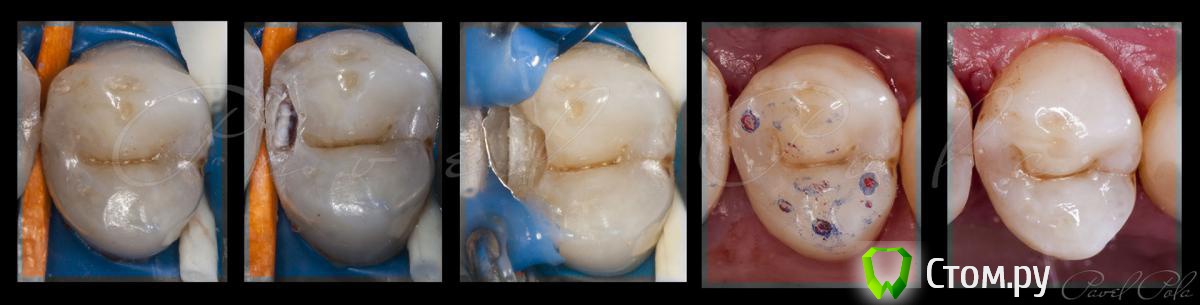

M@estro Опубликовано 22 сентября, 2014 Автор Поделиться Опубликовано 22 сентября, 2014 http://s020.radikal.ru/i702/1409/14/d82d4926b038.jpg 1.4 . Синяя копирка - 40 микрон,красная - фольга 8 микрон. 8 Ссылка на комментарий

M@estro Опубликовано 23 сентября, 2014 Автор Поделиться Опубликовано 23 сентября, 2014 Сначала 40 микрон,потом 8,сразу,не пришлифовывая. В центре синей-красная точкаточка,это и есть суперконтакт. Только прикусить до контакта,бе латеротрузий Ссылка на комментарий

Л Ю С Я Опубликовано 24 сентября, 2014 Поделиться Опубликовано 24 сентября, 2014 M@estro,но. Тут же 4 суперконтакта, какой убирали? Ссылка на комментарий

M@estro Опубликовано 24 сентября, 2014 Автор Поделиться Опубликовано 24 сентября, 2014 M@estro,но. Тут же 4 суперконтакта, какой убирали? 4 суперконтакта, 3 из которых на своих тканях) поэтому никакой) Когда "завышает", то пробивает только в месте завышения. Ссылка на комментарий